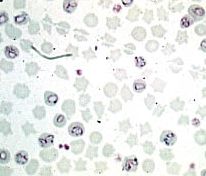

Babesia perroncitoi、小形のバベシアで虫体は大部分が径0.7~2.0㎛の環状分布は狭く、スーダンとサルジニアがあります。ヒトコブラクダにはT.camelenis、トルキスタン、エジプト、ソマリアに分布し病原性は弱い、その他...